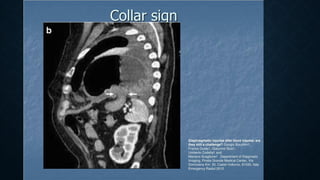

• Signs of diaphragmatic injury:

• The collar sign (or hourglass sign) : a waist-like constriction of the herniating hollow viscus

from the abdomen into the chest at the site of the diaphragmatic tear, which is classical for

diaphragmatic rupture.

• The dependent viscera sign: when a patient with a ruptured diaphragm lies supine at ct

examination, the herniated viscera (bowel or solid organs) are no longer supported

posteriorly by the injured diaphragm and fall to a dependent position against the posterior

ribs.

• Segmental non-recognition of the diaphragm.

• Focal diaphragmatic thickening.